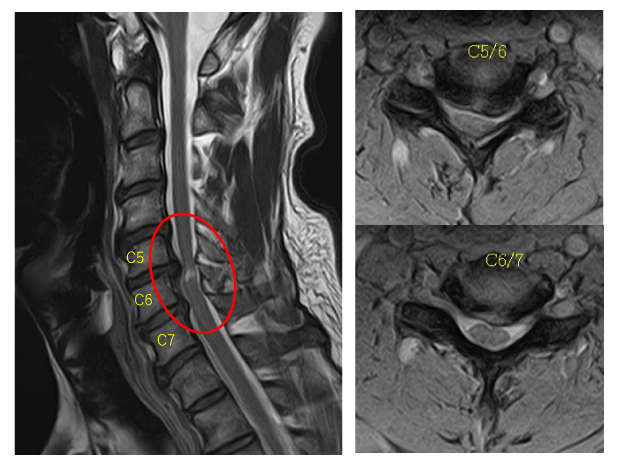

頸椎とは、脊柱の首の部分を指します。 C1 ~ C7 椎骨として知られる 7 つの骨で構成されています。脊柱管は背骨の中心を通るトンネルです。この管の中には、首の底から腰の底まで伸びる脊髄を構成する神経の集合体があります。

- MRI スキャン: MRI は、靱帯、椎間板、神経根など、脊椎周囲の軟組織の問題の診断に役立ちます。